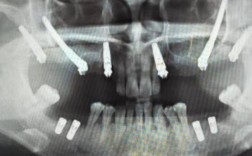

- 种植牙前的CT检查是评估骨量的金标准,提供了三维立体的精确信息。

- 骨量包括骨高度、骨宽度、骨密度和骨形态,这些指标共同决定了种植体的选择、植入方案以及是否需要额外的骨增量手术。